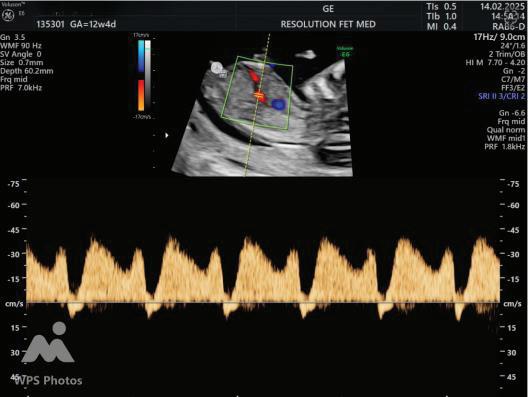

The first trimester— spanning from conception to 13+6 weeks—is no longer considered a “blind phase” of pregnancy. With the evolution of highresolution ultrasound, color Doppler and advanced biochemical screening, this period has transformed into a window of opportunity for early fetal evaluation, risk prediction and preventive strategies.

First-trimester fetal evaluation is not limited to dating the pregnancy or confirming viability—it is the foundation of predictive, preventive, and personalized obstetric care.

2. NUCHAL TRANSLUCENCY (NT) SCAN

• Done @11–13+6 weeks.

• CRL 45–84 mm.

• This is the cornerstone of first trimester screening.

1. NT is the sonographic appearance of subcutaneous accumulation of fluid behind the fetal neck, below the skin in the first trimester of pregnancy.

2. Measured in mid-saggital section only.

3. Measured between 11-14 weeks.

4. CRL between 45-84mm.

5. Magnified to include only head and upper thorax.

6. Fetus should be in neutral position.

7. Demostrate fetus separate from amnion.

8. Measurement should be ON to ON (cross bar of the callipers should be such that it’s hardly visible and merges with white line, not nuchal fluid).

During the scan more than one measurement should be taken and maximum value should be considered.